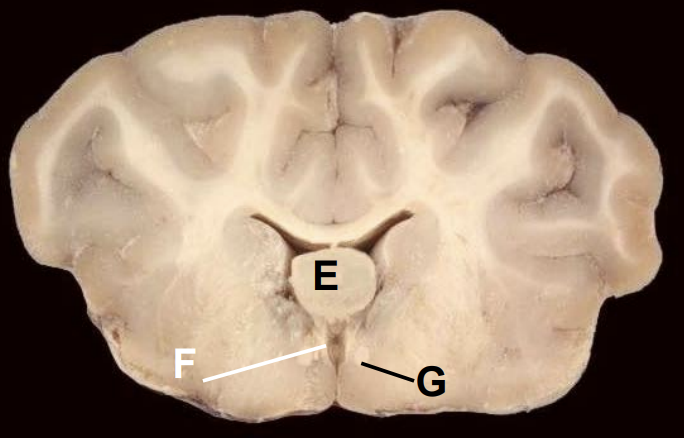

5

Thalamus

6

Third ventricle

7

Fornix